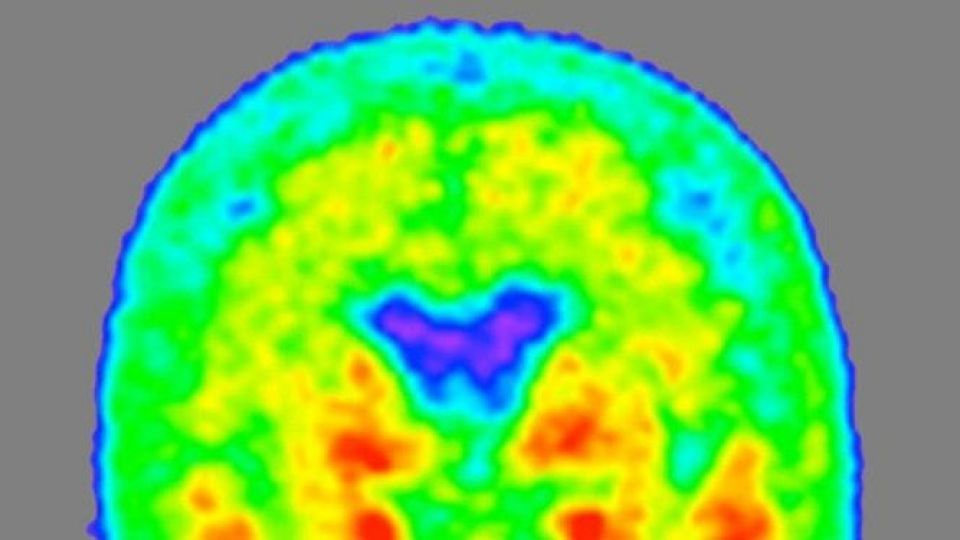

برای شناسایی نشانه های ابتلا به بیماری آلزایمر از طریق بررسی مایع نخاعی از یک روش اسکن وقت گیر و پرهزینه به نام پی ای تی استفاده می شود که از طریق آن نیز می توان برای شناسایی پروتئین تاو اقدام کرد. این روش بر روی یک نمونه صد نفری از افراد ۷۰ سال به بالا آزمایش شده که نتایج آن در مجموع رضایت بخش بوده است.